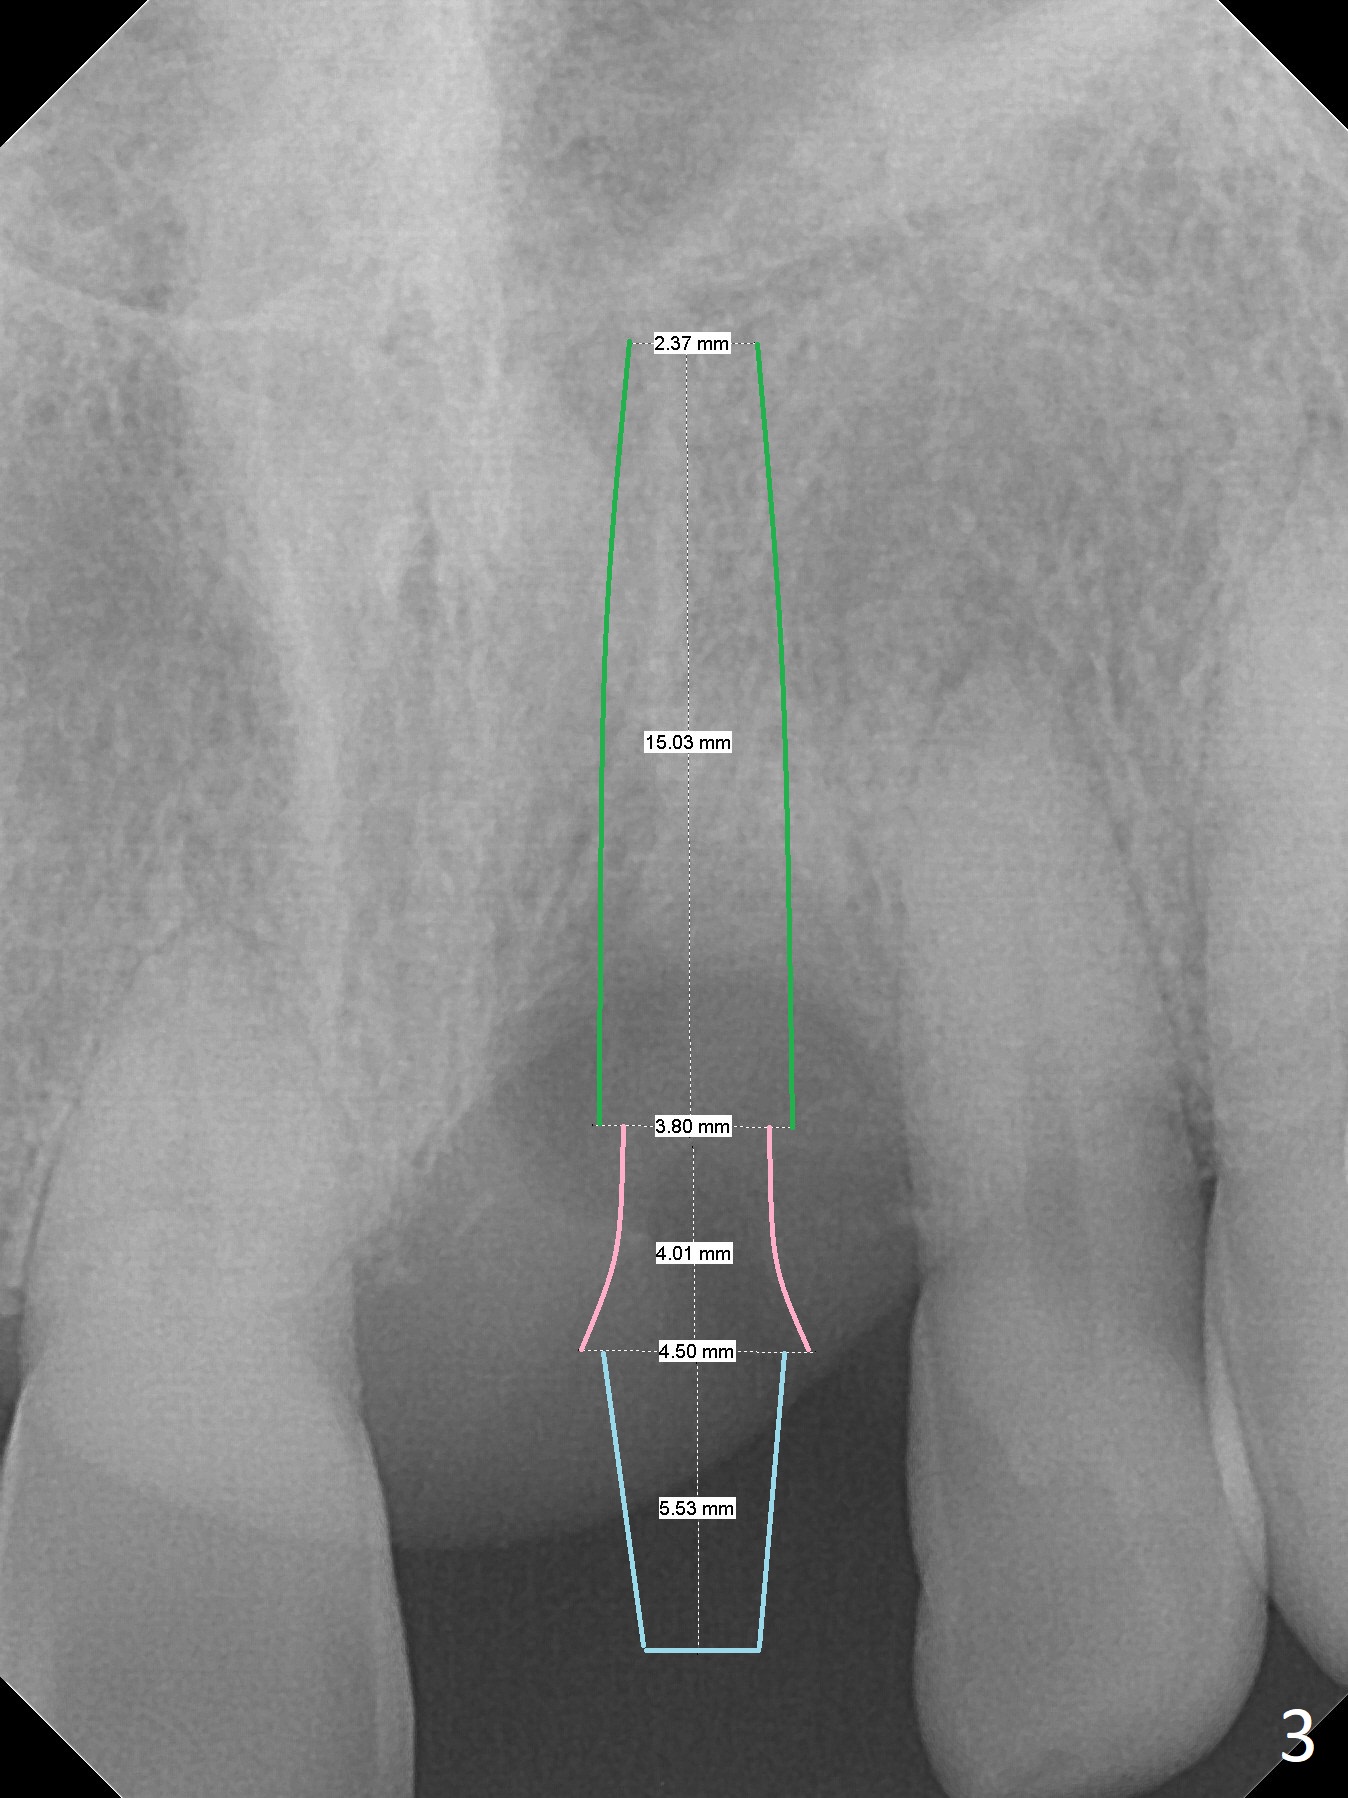

A 57-year-old man has lost the tooth #9 for 1-2 weeks (Fig.1,2). Although the buccal gingiva is recessive (cosmetically compromised), the middle and apical one thirds of the buccal plate appear to be minimally atrophic because of exostosis (Fig.1 *). An implant will be placed as palatal as possible (Fig.3). Use bone gauge to measure bone width. If the alveolus is atrophic, either use 3.5x13 mm implant or 1-piece (DIO or Tatum if there is a angulation problem). Prepare Planning Kit if IS implant is used. Adjust the opposing implant FPD, if needed.